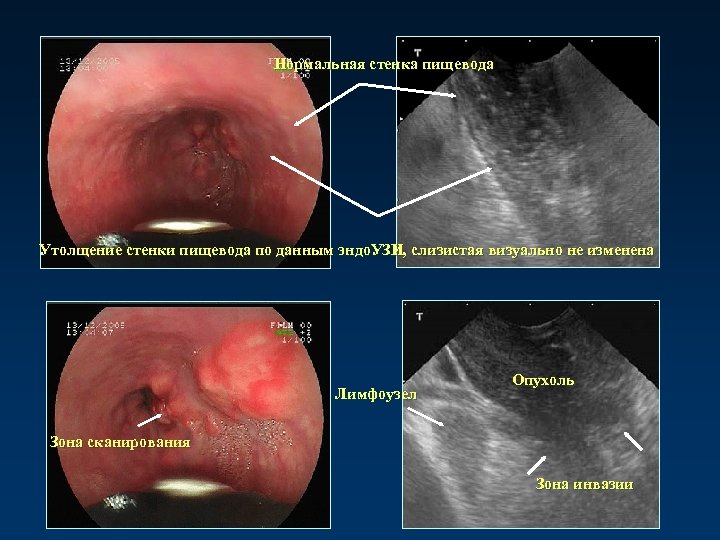

Эндоскопическая ультрасонография с использованием эндоскопа с линейным датчиком

Нормальная стенка пищевода Утолщение стенки пищевода по данным эндо. УЗИ, слизистая визуально не изменена Лимфоузел Опухоль Зона сканирования Зона инвазии